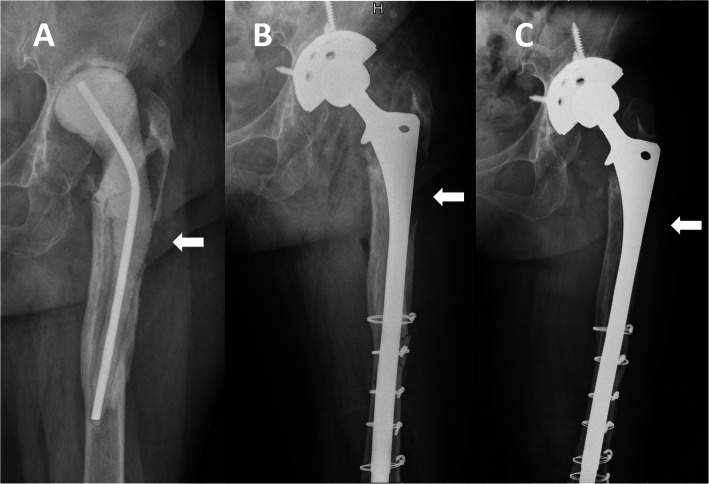

Fig. 2.

Anteroposterior radiographs of a 76-year-old man who underwent revision THA for a periprosthetic joint infection using extensively porous-coated stem alone. a Radiograph prior to stage 2 revision THA showing a Paprosky type IIIB femoral bone defect. b Postoperative radiograph at 6 months showing no bone restoration in the bone defect area (white arrow). c Postoperative radiograph at 5 years showing bone defects still existing and moderate stress shielding on both the medial and lateral sides